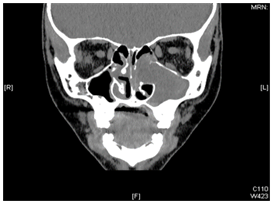

A 9 years old girl, presented with longstanding, left sided nasal obstruction and serosanguinous nasal discharge. She had been experiencing nasal obstruction and intermittent epistaxis for one year already. Her past medical history was otherwise unremarkable. The patient on anterior rhinoscopy, a bulge was detected, arising from the left nasal wall and impinging on the septum. The computed tomography (CT) examination was performed on a spiral scanner. The CT scan obtained following intravenous contrast administration revealed a large, inhomogeneously enhancing mass in the left maxillary sinus and nasal cavity (Figure 1–3). The nasal turbinates and the medial wall of the maxillary sinus had been eroded by the mass. There was also a bony remodeling in the anterior wall of the maxillary sinus. Because of the suspicion of sinonasal cancer, a biopsy was taken to obtain tissue from the nasal cavity and maxillary sinus. However, the biopsy revealed multiple submucosal dilated vessels filled with blood, fibrin deposition and organized thrombi stain for fungal organism negative, findings consistent with hemangioma. The microscopic examination showed dilated sinusoidal vascular channels in the stroma lining with an interconnecting fibrous wall covered with flat endothelium. The Lumina of these spaces were filled with blood. The histologic features were most compatible with cavernous hemangioma (Figure 4). On follow up, patient improvement regarding nasal obstruction and less nasal bleeding.

Figure 1 Coronal CT scan showing a large expansile lesion occupying mainly the left maxillary antrum with distended and thinned out bony wall of the left maxillary cavity, the lesion extends to the left nasal cavity and ethmoidal air cells with partial obliteration of the left nasal cavity.